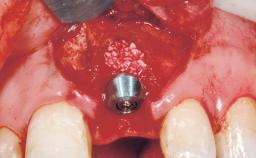

Late Flapless Placement of an Implant in a Maxillary Left Central Incisor Site

Bone Augmentation Horizontal|Staged

Augmentation Materials Xenogenous|Membrane

Soft Tissue Grafting Simultaneous

Bone Volume Deficient horizontally, requiring prior grafting